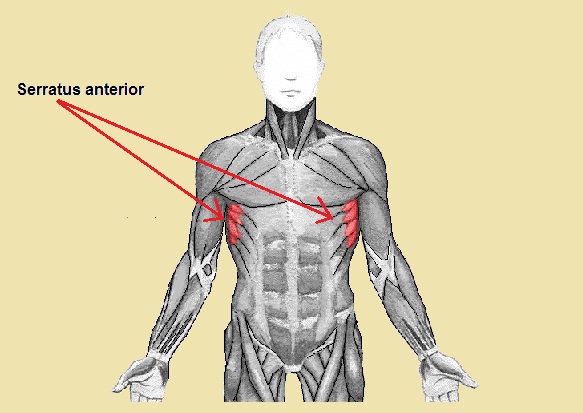

El serrato anterior o serrato mayor como también se le conoce, es un músculo par ubicado a ambos lados del tórax (lado derecho e izquierdo) que específicamente cubre la parte lateral de las primeras costillas (parte superior del tórax). Su nombre proviene del latín musculus serratus anterior.

El serrato anterior o mayor, es un músculo delgado y plano, de ubicación superficial. Su superficie es dentada (en forma de sierra), de allí proviene su nombre “serrato”. Presenta haces largos y delgados. Para palparlo, basta colocar los dedos sobre uno de los costados.

Debajo del serrato anterior se encuentra la jaula torácica y por detrás de este se relaciona con el músculo subescapular, y por delante con los pectorales mayor y menor. Entre el serrato anterior y las estructuras mencionadas se encuentra interpuesta una membrana célulo-grasosa que recubre todo el músculo y lo ayuda a deslizarse.